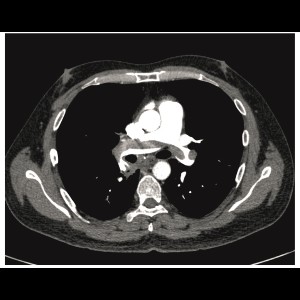

Acute pulmonary embolism being the first presentation of undetected HIV infection

Acute pulmonary embolism being the first presentation of undetected HIV infection

Acute pulmonary embolism being the first presentation of undetected HIV infection

Acute pulmonary embolism being the first presentation of undetected HIV infection